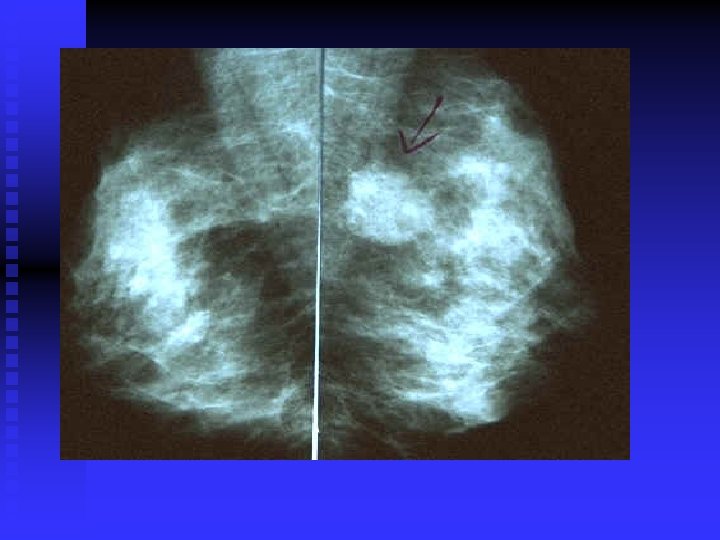

Left breast (L) contains an irregular carcinoma that is producing considerable spiculation, nipple retraction

Left breast (L) contains an irregular carcinoma that is producing considerable spiculation, nipple retraction (arrow), and skin thickening. Right breast (R) contains fibroadenoma.